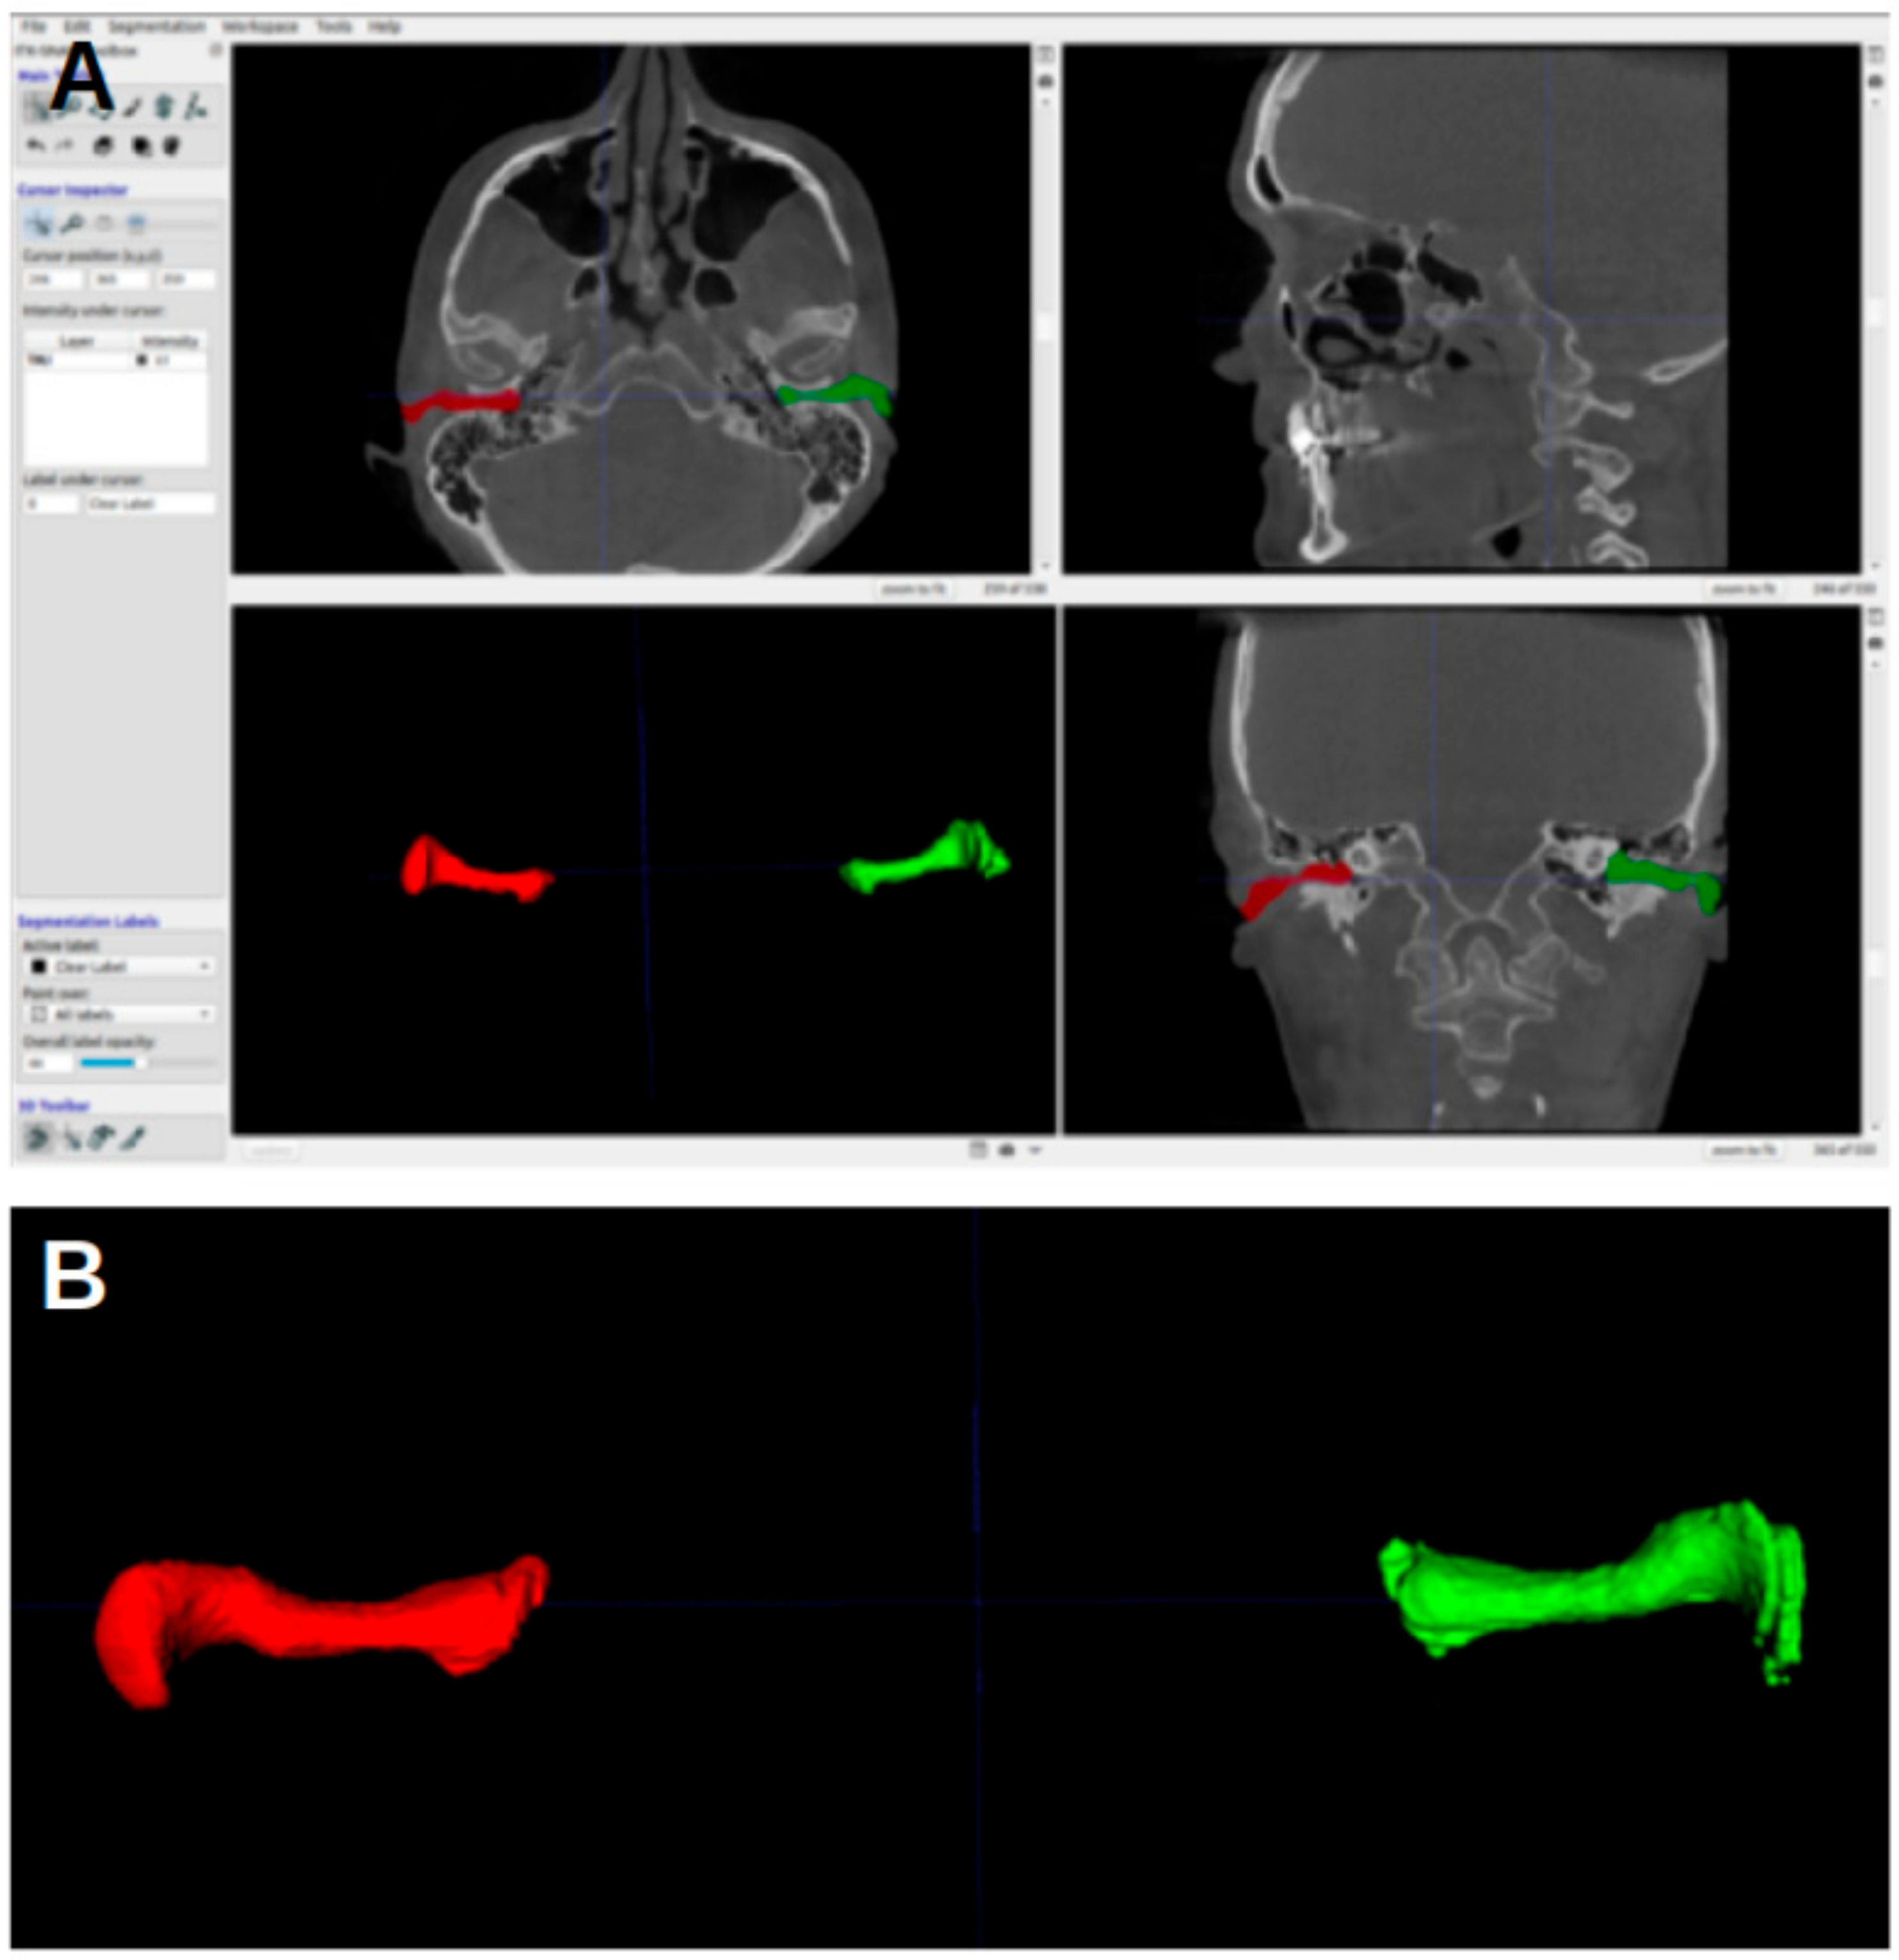

Figure 3 shows the ITK-SNAP window with segmentation, with the axial view shown in the upper-left image. In the first four landmarks, the crosshairs were placed such that they fell inside the segmentation of the acoustic meatus.

Figure 3. ITK-SNAP window. (A) Axial view. (B) Sagittal view. (C) Three-dimensional rendering of acoustic meatus. (D) Coronal view.